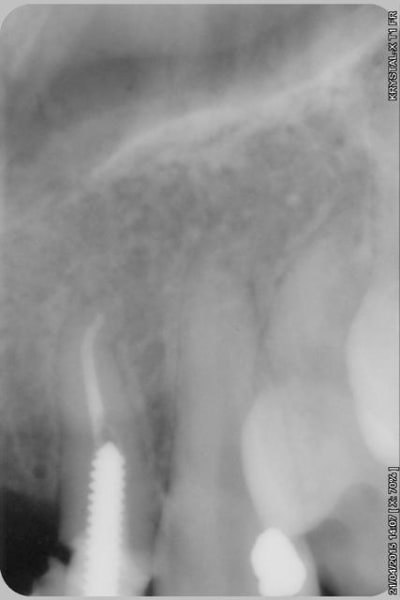

sur-traitement, pompe à fric, assassinat ...etc.. afin d'éviter tout ça je soumet à votre sagesse un cas sympa.

Patiente sympa, 30 ans, un bridge ceramo-métal fait il y a 10 ans, en fin de vie.

En réalité je sais déjà ce que je vais faire, mais implants, bridge ou pourquoi pas adjointe???

Les endo et les IC dans les 12-22 sont sublimes...et ça a durer 10 ans....incroyable...Il y a pas de la paro aussi ?

étonnant en effet... et encore plus étonnant, ce qui n'arrive jamais le radiologue (qui est parfaitement compétent normalement) a inversé la droite et la gauche.